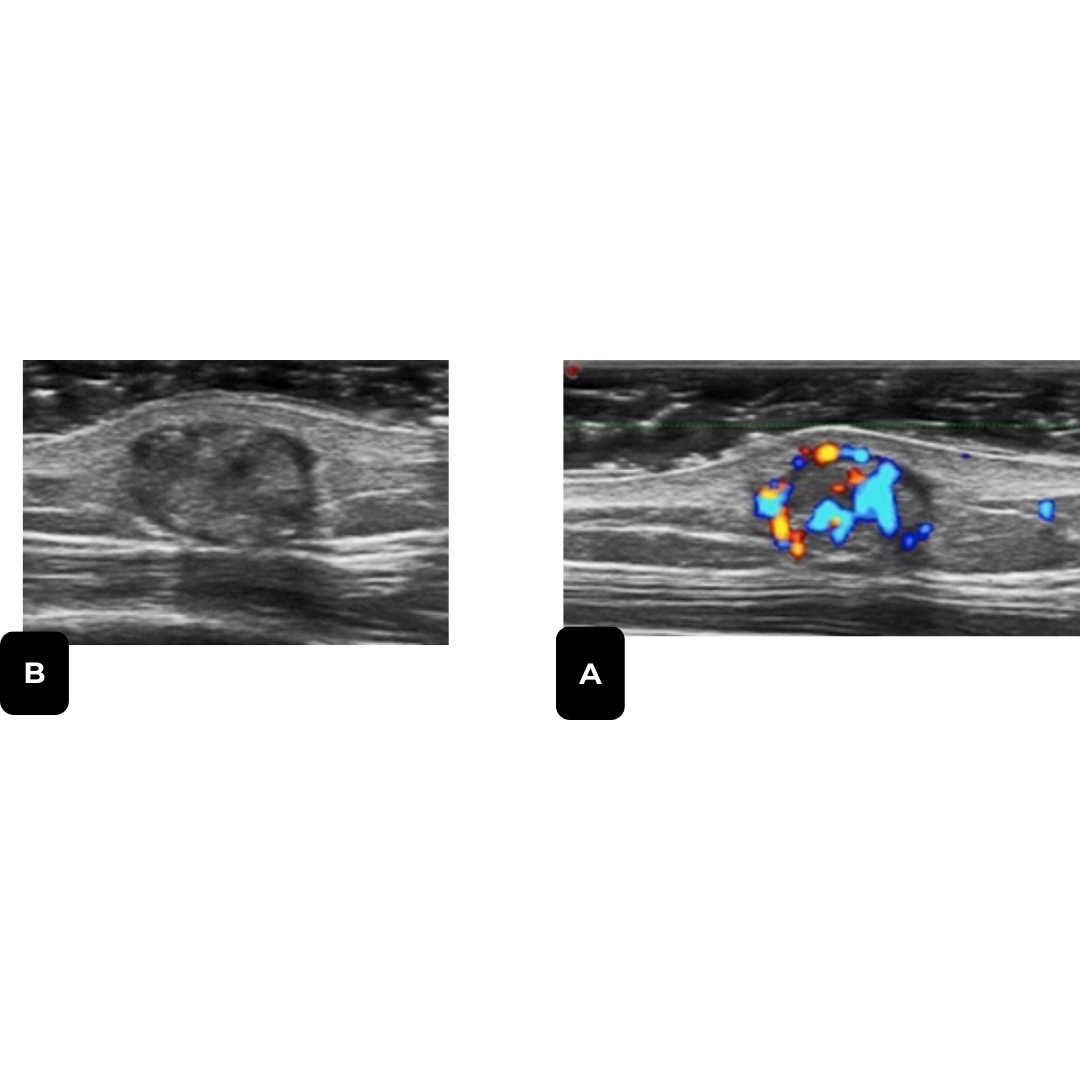

Nódulo bien definido, heterogéneo, predominantemente hiperecogénico, con halo fino hipoecogénico, con puntos hiperecogénicos internos sugerentes de calcificaciones internas, pueden presentar áreas quísticas internas, sombra acústica posterior, vascularización al Doppler se describe un 70 % de los casos periférica, pero también podemos encontrarla central y mixta (imagen 4).

Imagen 4: A) Pilomatricoma, nódulo solido heterogéneo, con área quística interna, halo hipoecogénico, con microcalcificaciones, sombra acústica posterior. B) patrón vascular variable con vascularización periférica y central.